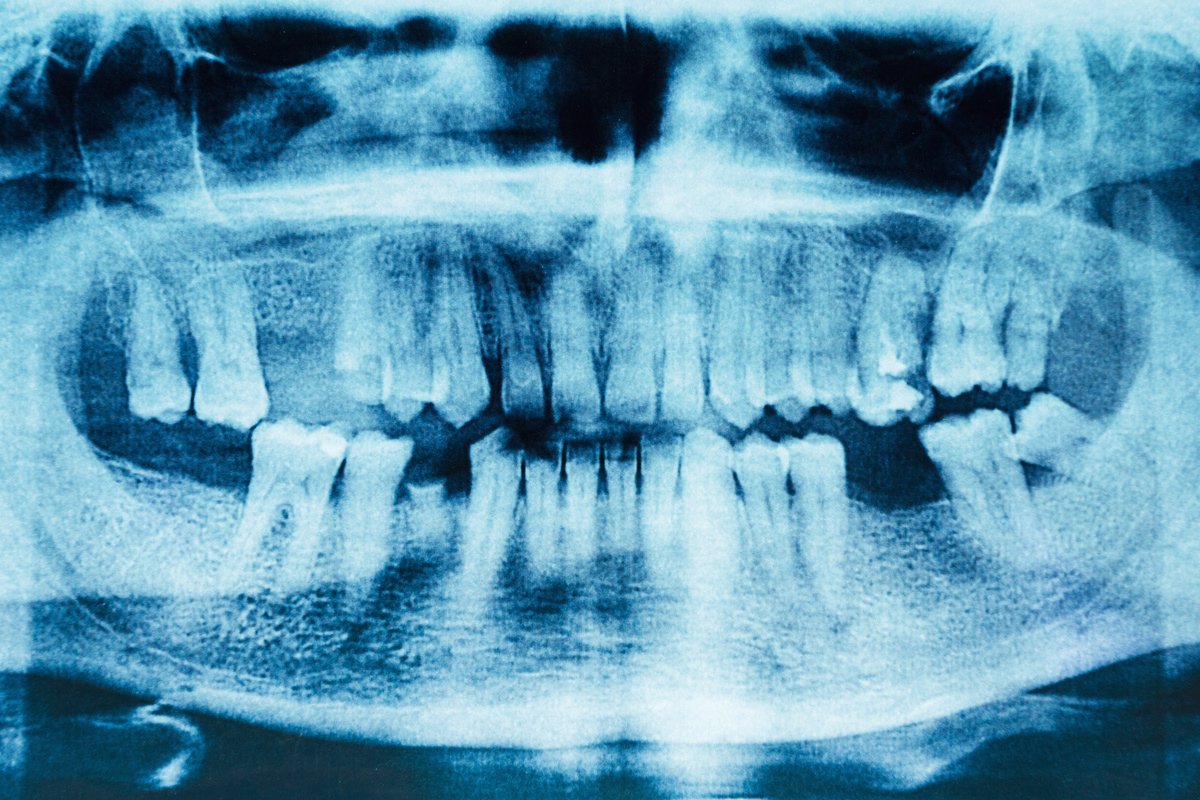

Getting a tooth extraction can leave your smile feeling incomplete, and you may wonder how long you’ll have to wait before restoring your confidence and your smile’s appearance with a dental implant. The answer depends on several factors, including the condition of your jawbone, your overall health, and the type of implant procedure that’s right for you. At Richard Hardt,